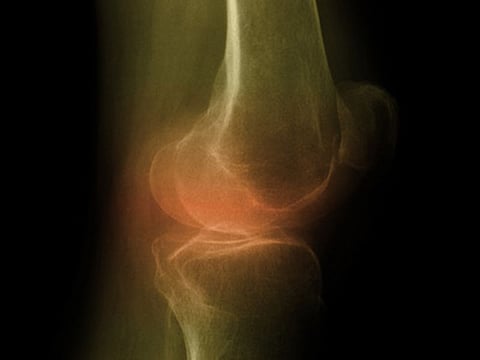

LUNES, 14 de agosto de 2017 (HealthDay News) -- Las tasas de osteoartritis de la rodilla se han duplicado en Estados Unidos desde los años 40, pero no solo porque los estadounidenses vivan más tiempo y pesen más, sugiere un nuevo estudio.

"Cuando el cartílago se erosiona, y los dos huesos que forman la articulación entran en contacto directo, se rozan entre sí, haciendo que se desarrolle un pulido parecido al cristal", dijo Wallace. "Ese pulido, llamado eburnación, es tan claro y obvio que podemos usarlo para diagnosticar con mucha precisión la osteoartritis en restos esqueléticos".